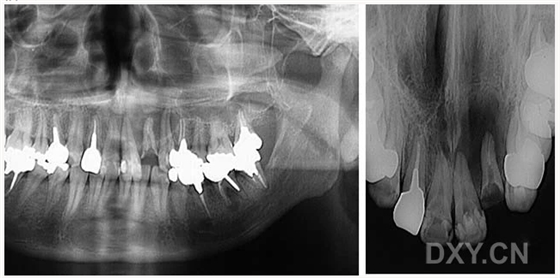

成釉細(xì)胞瘤

鼻鄂囊腫